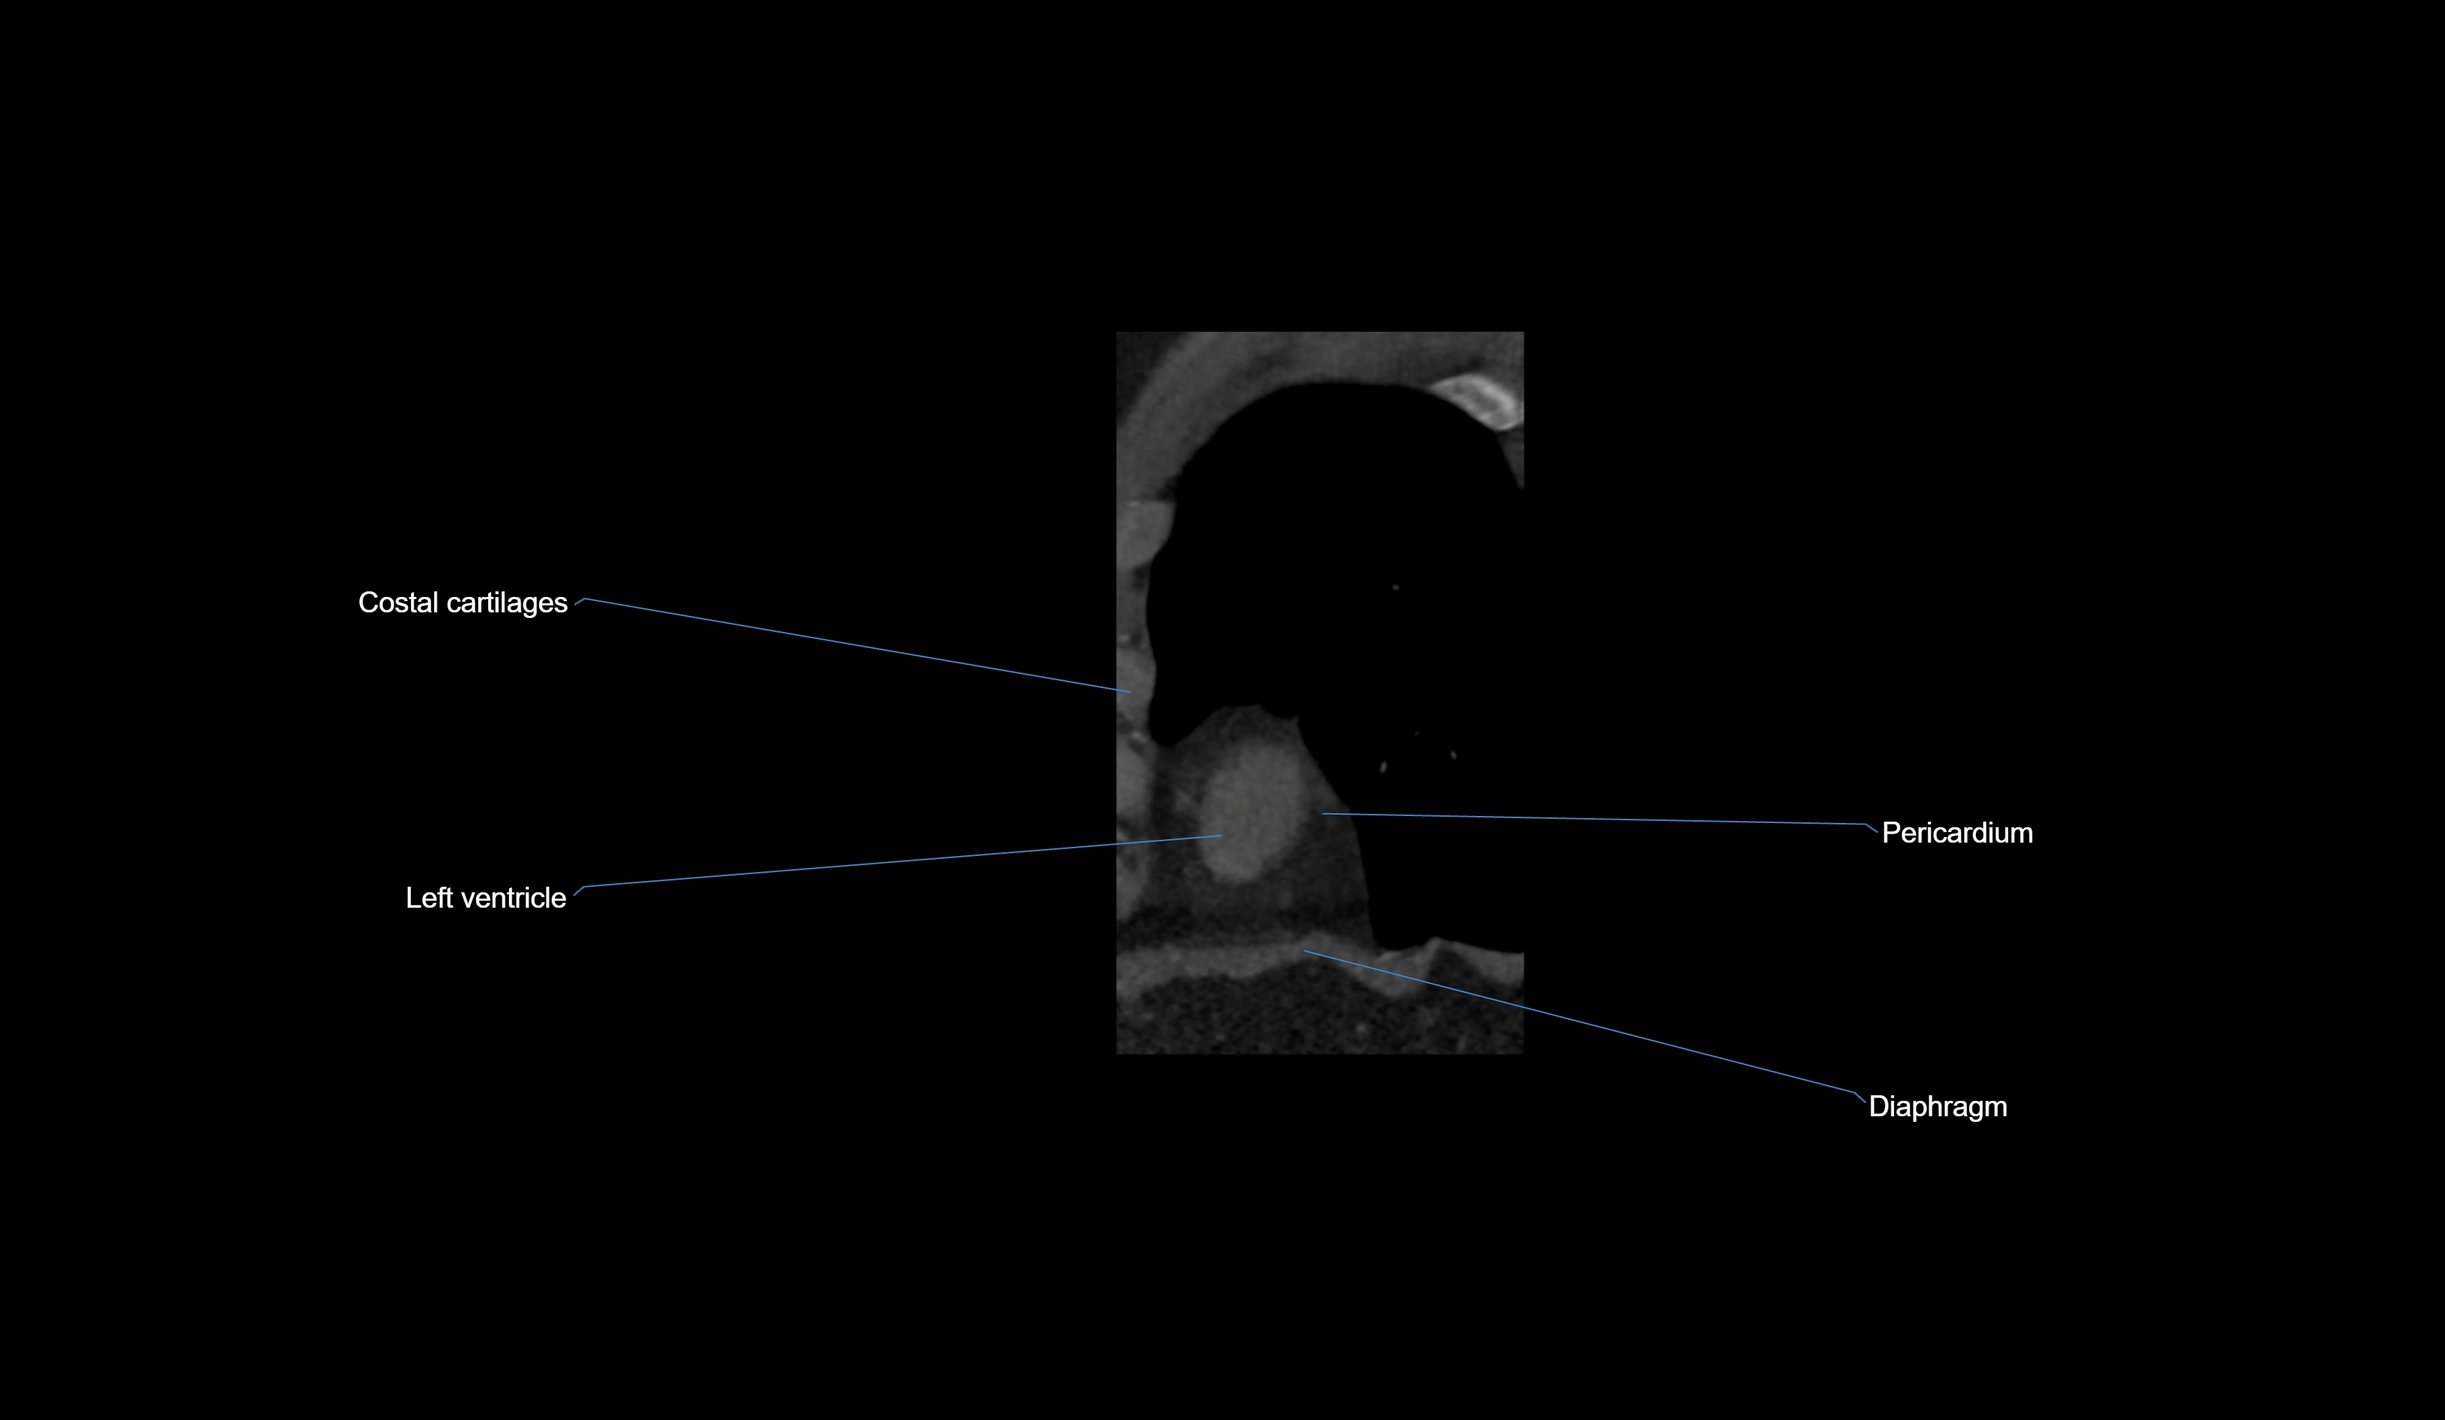

- Left ventricle

- Pericardium

- Diaphragm

- Costal cartilages